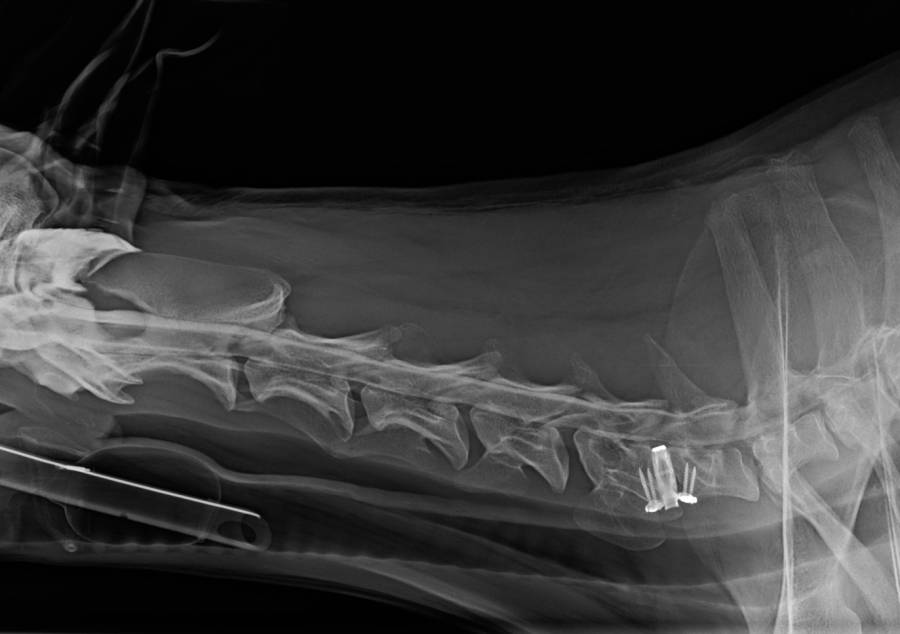

- C-Lox Schablone unter C-Bogen Kontrolle einsetzen um die Implantatgröße zu bestimmen

alternativ an benachberter BS messen - C-Lox-Cage fest einsetzten und C-Lox-Distractor entfernen

- Cage anschrauben (die Ohren könne gebogen werden um besseren Knochenkontakt herzustellen)

- Anschrauben: mit der Bohrhülse werden mit dem beigelegten Bohrer / einem 1,8 mm Borhdraht Markierunge für die selbstschneidenden Schrauben gesetzt (Länge im vorhinen bestimmen